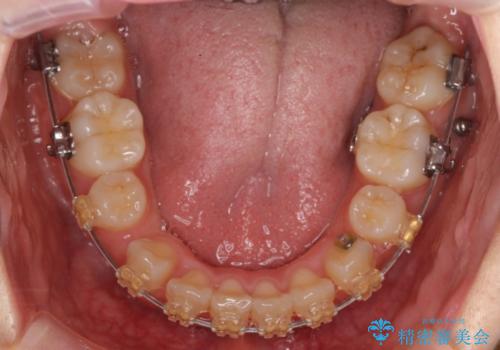

- 矯正装置

- 審美装置

成人式の1年前から矯正をはじめ、成人式前に上の前歯の装置を一時的にとりました。